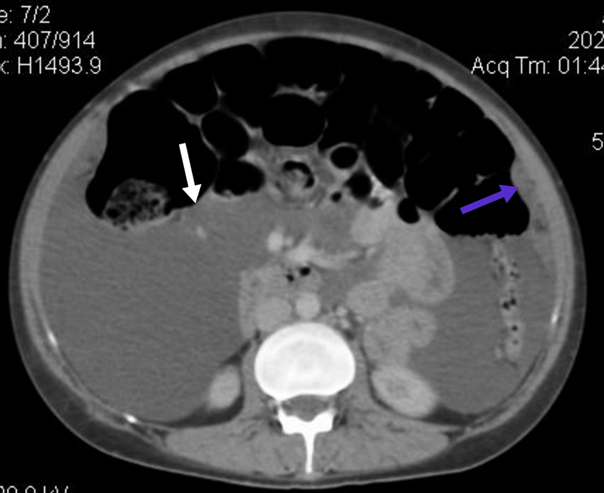

The uterus was

normal in both size and shape. Focal lesions were not observed. Multiple

enlarged, rounded, and enhancing lymph nodes are seen in the pelvis. Gross

abdominopelvic ascites were observed. No scalloping of the abdominal viscera

was observed, and multiple large soft tissue density-enhancing deposits of

variable sizes were seen in the omentum, predominantly on the left side of the

abdomen measuring 2.8 x 1.5 cm as shown in (figure 2).

figure 2. White arrow showing ascities. Blue arrow showing omental

deposits.